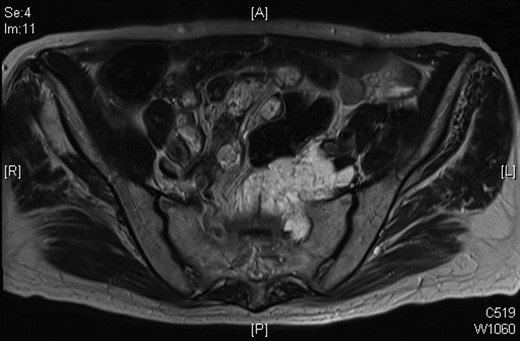

In October 2009, a magnetic resonance imaging (MRI) scan of his spine was arranged due to leg pain thought to be of neurological origin. This did, indeed, showed marked L5 and S1 spinal stenosis; however, it also showed an irregular mass in the left side of the pelvis anterior to the sacrum and abutting the distal rectum and the emerging left S1 nerve root on the anterior surface of the sacrum. Overall, the dimensions were 3.6 × 4.3 × 3.8 cm. There was a similar area of soft tissue on the previous CT of September 2008. The possibility of a further slow-growing rectal recurrence was raised. This was discussed at multidisciplinary team meeting and as the mass was cold on PET scan in March 2009, it was decided to repeat the PET scan, which was done in February 2010 and November 2010, and the mass again showed no uptake.

MRI scan of 2009 showing a mucinous mass in the left side of the pelvis below the anastomosis from his original sigmoid colectomy.